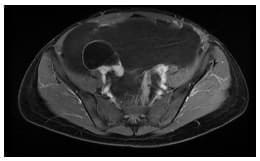

Se realizó una resonancia magnética de abdomen y pelvis que demostró la ocupación de todos los recesos peritoneales con líquido complejo de diferentes captaciones y septos multiloculados, la ocupación del espacio subfrénico derecho debido al desplazamiento tanto del hígado en sentido superior, como de las asas intestinales incluyendo el colon derecho en sentido central y en sentido posterior rechazando el colon descendente. No había compromiso retroperitoneal.

Se encontró además una lesión quística dominante adyacente al pedículo ovárico derecho sin conformarse propiamente una masa ovárica, lo que hizo sospechar el origen en la trompa.

Debido a la presentación clínica y a los resultados de la resonancia, se sospechó un pseudomixoma peritoneal de probable origen apendicular (Figuras 1-3).

Figura 1. Resonancia magnética abdominal en corte T1 con supresión grasa post contraste

(corte axial). La trompa derecha está adherida a la lesión quística pura, sin contenido

proteínico ni sanguinolento, que aparentemente corresponde a la lesión quística

inicial de la paciente.